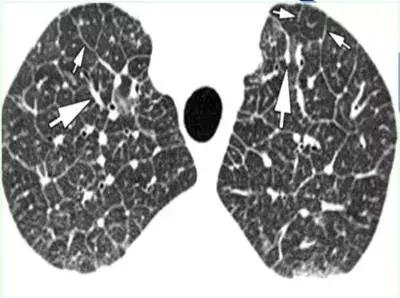

CT征象八:碎石路征

碎石路征(Crazy paving appearance):在HRCT上,表现为地图状分布的、重叠有网状的光滑细线影的磨玻璃影;最常见于肺泡蛋白沉着征。

细线影为小叶间隔水肿增厚,或蛋白样物质沉积于邻近小叶间隔的气腔内所致。

碎石路征(Crazy paving appearance)

碎石路征:肺泡蛋白沉着症(PAP)